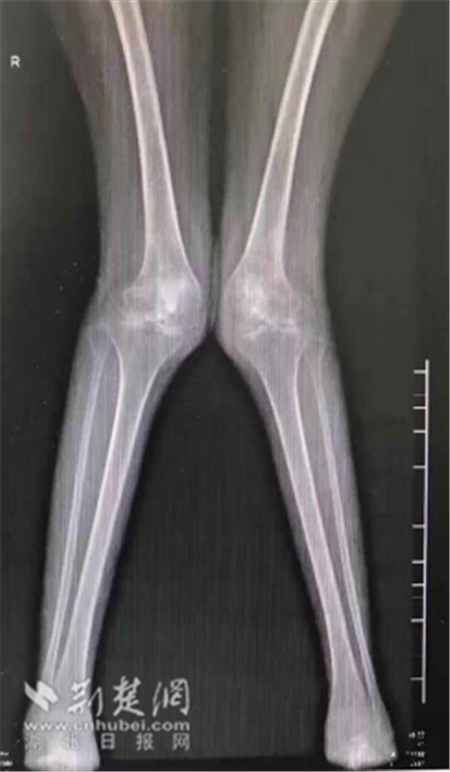

影像检查显示小叶双腿严重畸形外翻。

爸爸常年在外面工地上干活,妈妈在家照顾生活不能自理的小叶。爱她的爸妈,不甘心女儿从此无法行走,一年前带着小叶到武汉市第一医院骨关节外科诊治。副主任医师涂峰介绍,小叶的双膝关节当时已外翻30度,属于重度畸形,唯有手术才能解决行走问题。然而小叶的病情,相比普通的膝关节置换患者来说,手术难度更大,风险更高。90%的病人都是膝关节内翻畸形,而小叶属重度膝关节外翻,无疑加大了手术难度;风险在于她是一个系统性红斑狼疮患者,长期服用大剂量的激素类用药,导致抵抗力下降,大大增加了伤口感染几率。